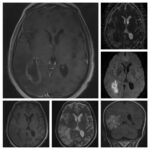

Neurosurgery and neuroradiology always go hand in hand. This little weekly activity is going to enhance the scan reading skills of our audience in an interactive way. Waiting for the answer for a week will keep the curiosity alive and will keep our target audience hooked to the website. It will prove to be a seamless share of knowledge and reading skills.

Dr. Saqib Kamran Bakhshi started the PANS Weekly Image Challenge in 2022, and his creativity and efforts made it a popular activity; engaging trainees and consultants in Pakistan and abroad.